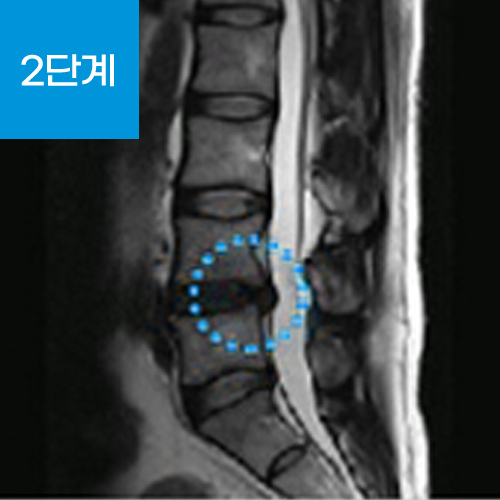

추간판(디스크) 중심에는 수핵과 수핵을 감싸는 섬유륜이라는 막으로 구성되어 있는데 추간판 탈출증이란 척추 뼈와 뼈 사이에서 완충 작용을 해주는 추간판(디스크)이 퇴행성 변화나 외상 등으로 추간판의 탄력이 저하되거나 손상되었을 때 수핵이 척추 바깥으로 탈출(튀어나옴)하게 되어 신경을 압박하여 통증을 느끼는 질환입니다.

손상된 디스크는 주변 신경을 자극하여 통증을 유발하는데 이것을 소위 '디스크'라 불리는 '추간판 탈출증'입니다.